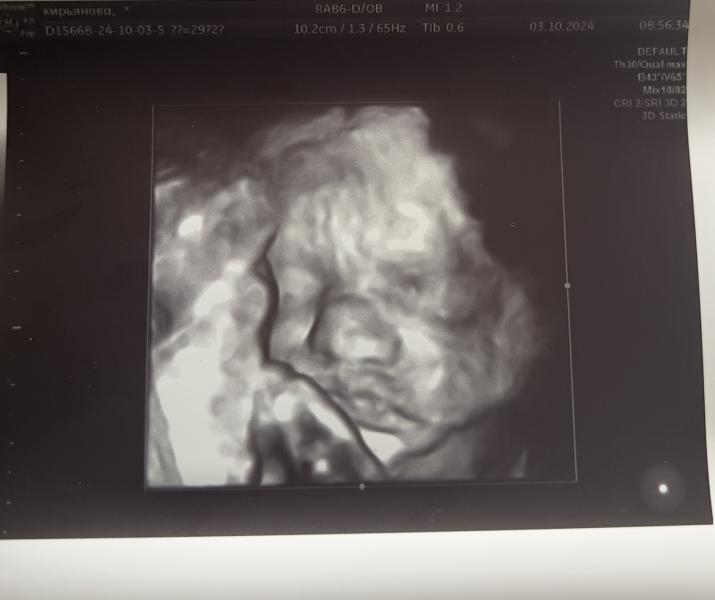

Вот такая губастая булочка получилась у нас ❤️

Дамочка не хотела позировать, то отворачивалась, то прикрывала лицо ногами 🤣

Главное все хорошо 🙏🏼 по весу она набрала отлично, так что про слово «маловесный» можно окончательно забыть 😁

Уже 1311 грамм весим

По узи поставили 29.5 срок